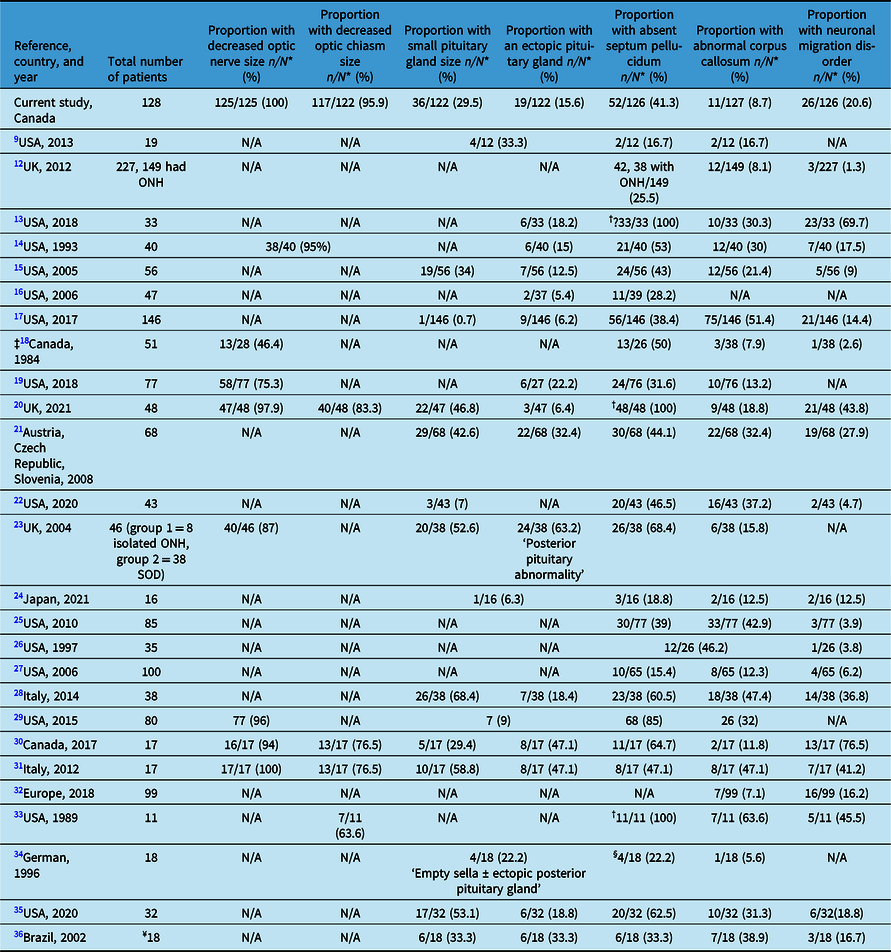

Table 2 shows the prevalence of the main abnormal neuroimaging features in patients with ONH/SOD from 26 studies in comparison with our cohort. Reference Mohney, Young and Diehl9,Reference Atapattu, Ainsworth and Willshaw12–Reference Antonini, Grecco Filho, Elias, Moreira and Castro36 A recent study on risk factors in ONH/SOD in 111 of our 128 cases shows additional clinical details in conjunction with a summary of some of the neuroimaging features. Reference Salman, Ruth, Yogendran, Rozovsky and Lix37

Table 2: Radiological features in optic nerve hypoplasia and septo-optic-pituitary dysplasia (ONH/SOD) based on reports from the medical literature

N*: Number of patients with adequate neuroimaging; N/A: not available; †: part of the inclusion criteria; ‡: older study with outdated imaging modalities (13 of 38 had pneumoencephalograms, three ventriculograms, six cerebral angiograms, and 26 of 38 CT scans); §: cavum septum pellucidum; ¥: 18 had cerebral midline developmental anomalies and 11 had ONH, who were not analyzed separately.

Various neuroimaging abnormalities, and especially absent septum pellucidum and small pituitary gland size with or without hypopituitarism, have been described in patients with SOD. Reference Riedl, Vosahlo and Battelino21,Reference Birkebaek, Patel and Wright23,Reference Severino, Allegri and Pistorio28,Reference Alt, Shevell, Poulin, Rosenblatt, Saint-Martin and Srour30,Reference Wadams, Gupta, Novotny and Tebben35,Reference Antonini, Grecco Filho, Elias, Moreira and Castro36 Table 2 summarizes some of the neuroimaging findings reported in 26 studies from 5 countries (Canada, USA, Europe, Japan, and Brazil) across four continents. Reference Mohney, Young and Diehl9,Reference Atapattu, Ainsworth and Willshaw12–Reference Antonini, Grecco Filho, Elias, Moreira and Castro36 Most studies from the 1990s onward, when brain MRI resolution improved substantially, like our study confirmed the reduced sizes of the optic nerve(s) and optic chiasm on brain MRI in the majority of patients with ONH/SOD. Reference Ward, Connolly and Griffiths20,Reference Cemeroglu, Coulas and Kleis29,Reference Alt, Shevell, Poulin, Rosenblatt, Saint-Martin and Srour30

The prevalence of the various other neuroimaging abnormalities reported in our study generally falls within the ranges described in other studies (Table 2). Reference Mohney, Young and Diehl9,Reference Atapattu, Ainsworth and Willshaw12–Reference Antonini, Grecco Filho, Elias, Moreira and Castro36 In most studies, a small pituitary gland size was reported in less than 60% of patients and in many studies in about 30–55%, while ectopic posterior pituitary gland was described less frequently (<50%) and in many studies in 5–33% of patients. A wider range for the occurrence of absent septum pellucidum (17 and up to 100%) and a narrower prevalence range for abnormal corpus callosum (mostly 8–40%) have been reported across many studies. The wide ranges reported in Table 2 are likely due to the variable inclusion criteria among various study participants, source of the patients (i.e., general/specialized health care centers or clinics for example, neurology/endocrinology clinics), sample size, genetic/ethnic background of the patients, variable phenotype of SOD, selection bias of the study participants (those with more severe clinical or neuroimaging abnormalities are more likely to be included), the focus of the study (i.e., the neuroimaging abnormalities investigated), and type of study (i.e., clinical or radiological). Reference Benson, Nascene, Truwit and McKinney13